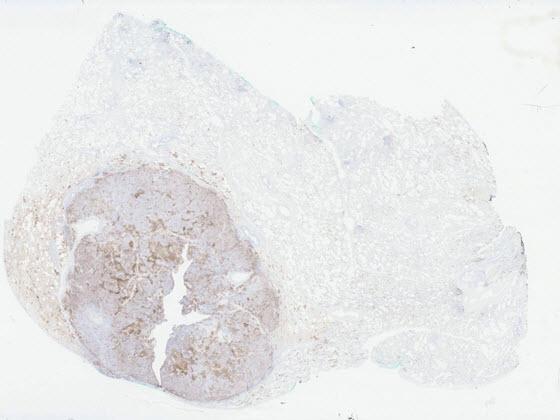

PD-L1 IHC digital slide (left) with Lung PD-L1 AI markup (right) identifying negative tumor cells (cyan), positive tumor cells (magenta), and other cells (yellow).

Developed by Indica Labs, the Lung PD-L1 AI solution leverages deep learning that standardizes scoring of PD-L1 IHC in non-small cell lung cancer (NSCLC) tissue samples. The algorithm reports quantitative results and markup images, including tumor detection, cell phenotyping based off the PD-L1 staining, and tumor proportion score (TPS).

After selecting an image, view the IHC slide in the viewer and the Lung PD-L1 AI results. Results include overlays and quantitative results. The first set of overlays prepare the tissue for analysis by identifying areas of analyzable tissue. The next overlay identifies areas of tumor in the sample. The final overlay identifies PD-L1 positive and negative tumor cells within the tumor area. Finally, quantitative results are displayed in the assay panel to the right and include a tumor proportion score (TPS).